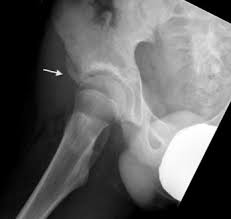

Pelvic Avulsion Fracture Symptoms Causes And Treatment from www.sportsinjuryclinic.net In the pelvis, the newly formed secondary centers of ossification, the apophyses, are the most likely portions of the bone to avulse. In adults, the ligaments and tendons tend to be injured first, whereas in children the bone may fail before. Physical therapy may also help a fracture heal more quickly than immobilization alone. Pelvis injuries range from the benign to life threatening. Your doctor might recommend that you use crutches to keep weight off the hip while it heals. Avulsion fractures are more common in children than in adults. Your doctor might recommend that you use crutches to keep weight off the hip while it heals. Aiis and ischial tuberosity fractures are at increased risk of developing future pain and nonunions, respectively.

Avulsion Fractures Of The Pelvis In Adolescents Eurorad from www.eurorad.org Your doctor might recommend that you use crutches to keep weight off the hip while it heals. An avulsion fracture is an injury to the bone in a location where a tendon or ligament attaches to the bone. When a small piece of the bone breaks off the main bone. Apophyseal avulsion fractures are usually the result of a sudden forceful concentric or eccentric contraction of the muscle attached to the apophysis. In the pelvis, the newly formed secondary centers of ossification, the apophyses, are the most likely portions of the bone to avulse. Your physical therapist will show you how to perform exercises that strengthen the bone and improve your range of motion. They usually happen when a bone is moving one way, and a tendon or ligament is suddenly pulled the opposite way. How good is recovery after pelvic fracture?

Physical exam should not be used to rule out a pelvic fracture in unconscious patients, but it can nearly definitively rule it in. What is pelvis avulsion fracture?1. Pelvic and hip apophyseal avulsion injuries in young athletes. Short talk about pelvic avulsion fractures with examples hopping you like it dr hisham alkhatib consultant radiologist. An avulsion fracture is when a tendon or ligament pulls a piece of fractured bone away.